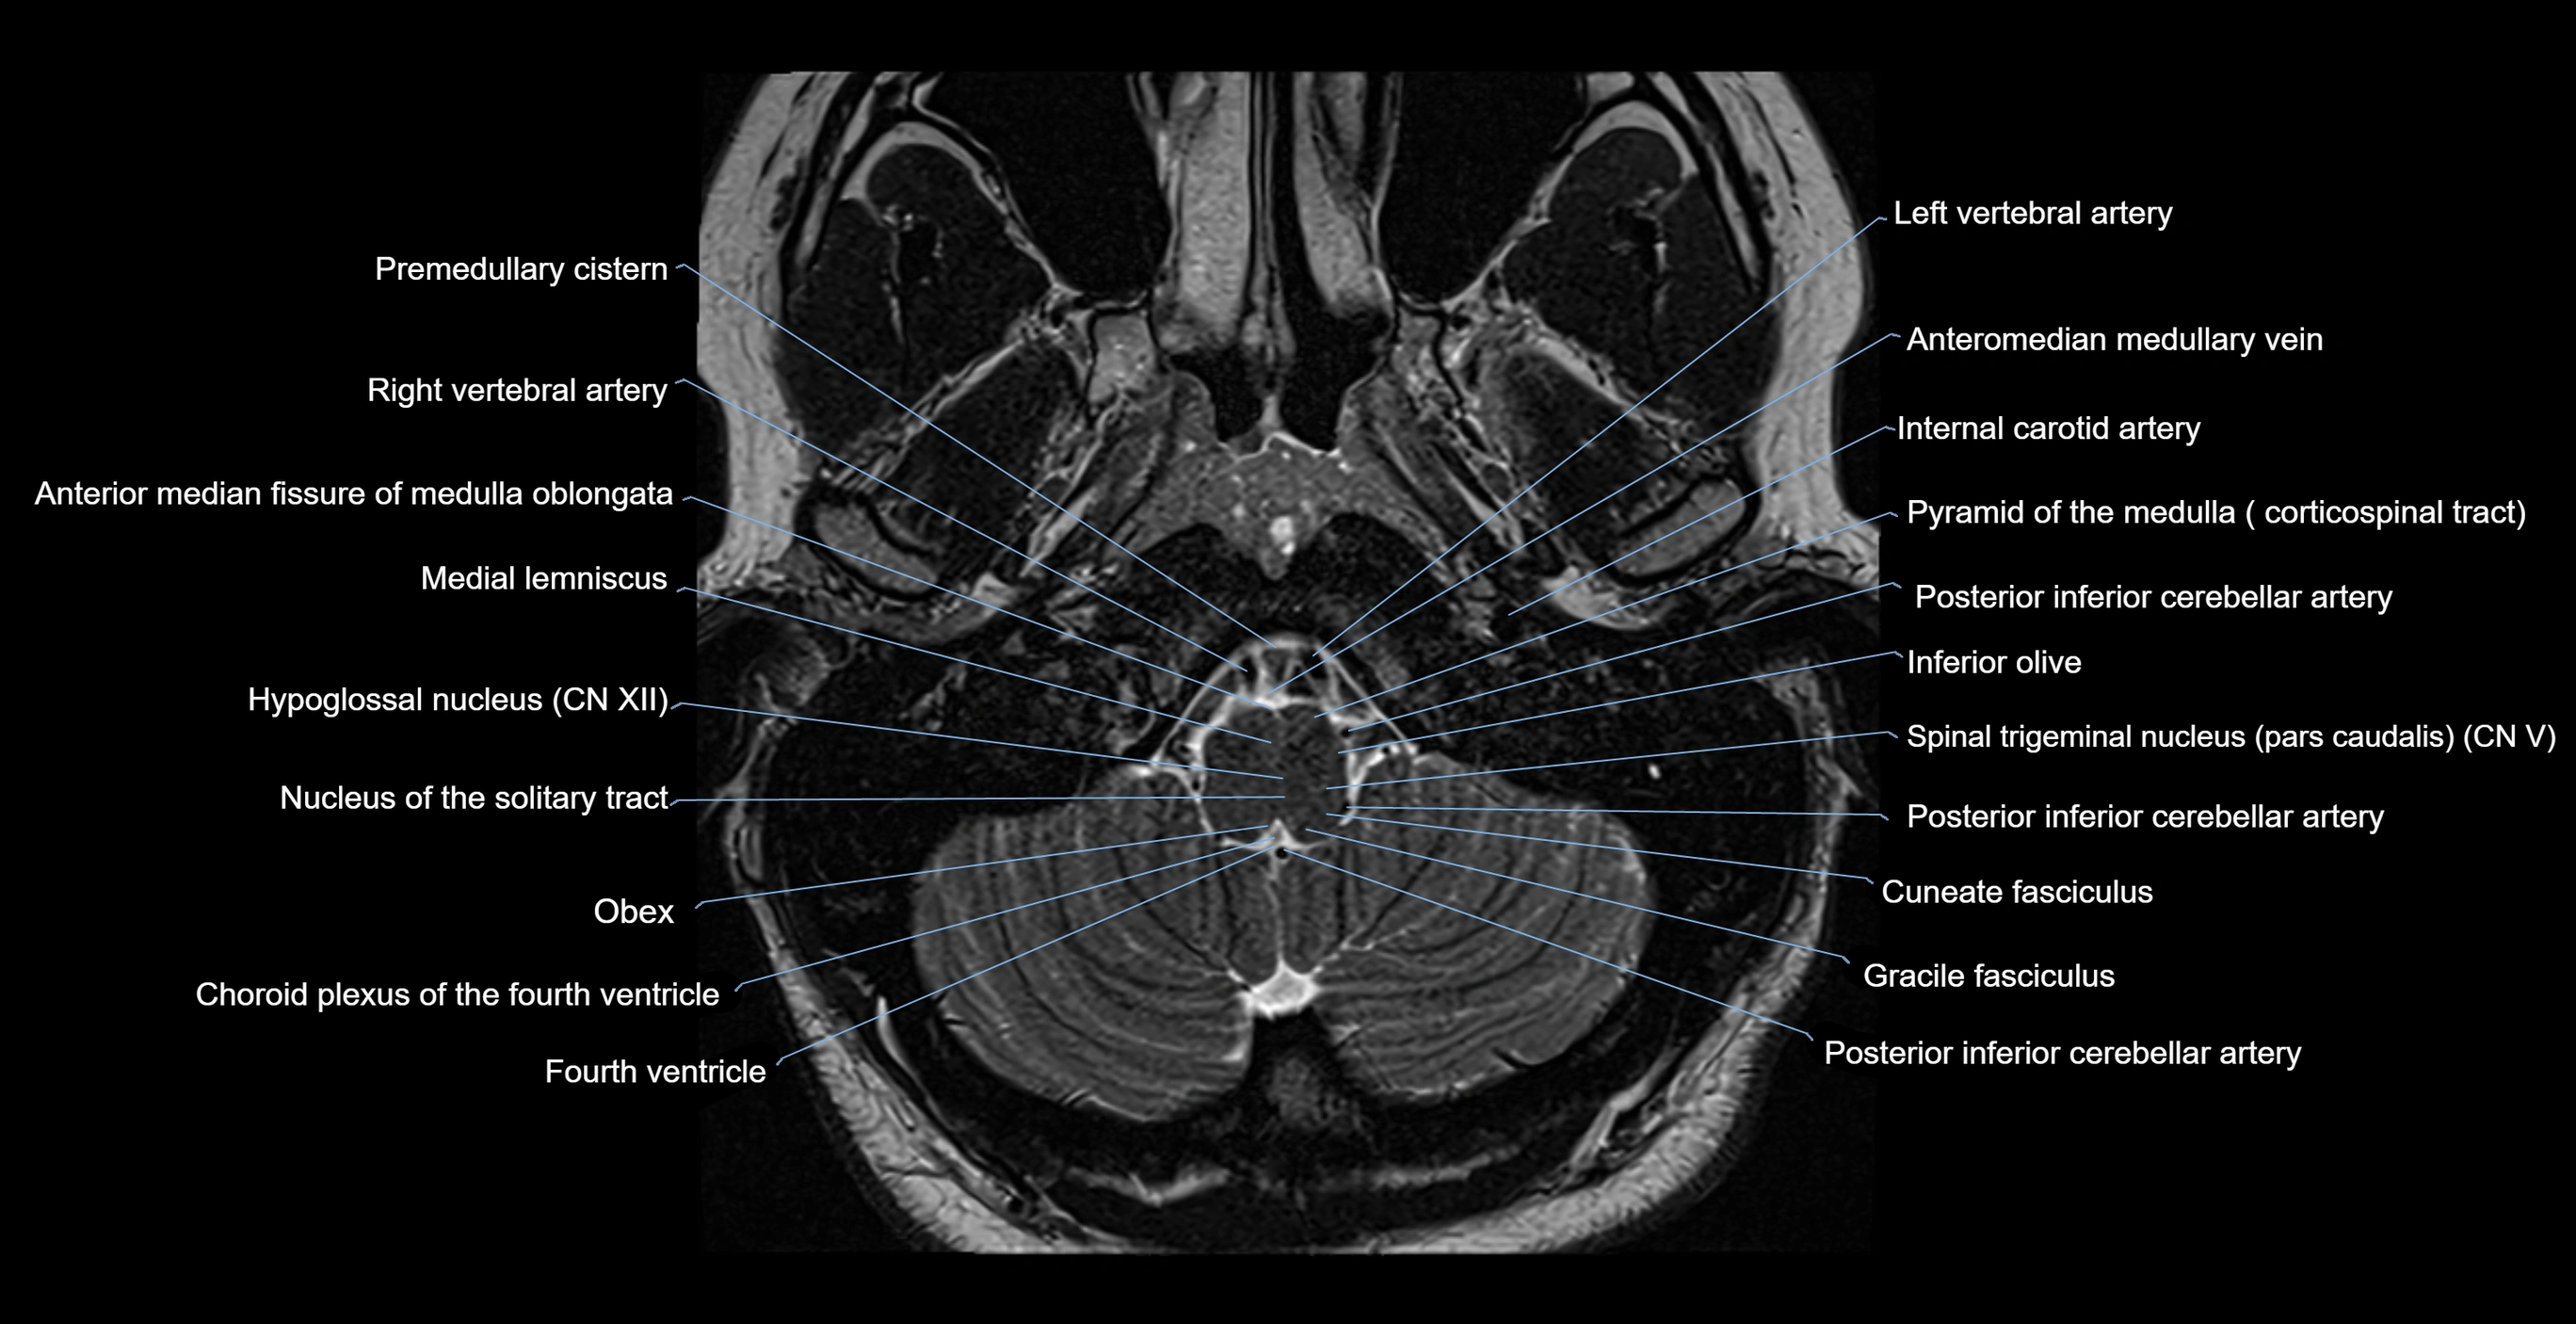

- Anterior median fissure of medulla oblongata

- Cuneate fasciculus

- Fourth ventricle

- Gracile fasciculus

- Hypoglossal nucleus

- Inferior olive

- Medial lemniscus

- Nucleus of solitary tract

- Obex

- Posterior inferior cerebellar artery

- Premedullary cistern

- Pyramid of medulla oblongata